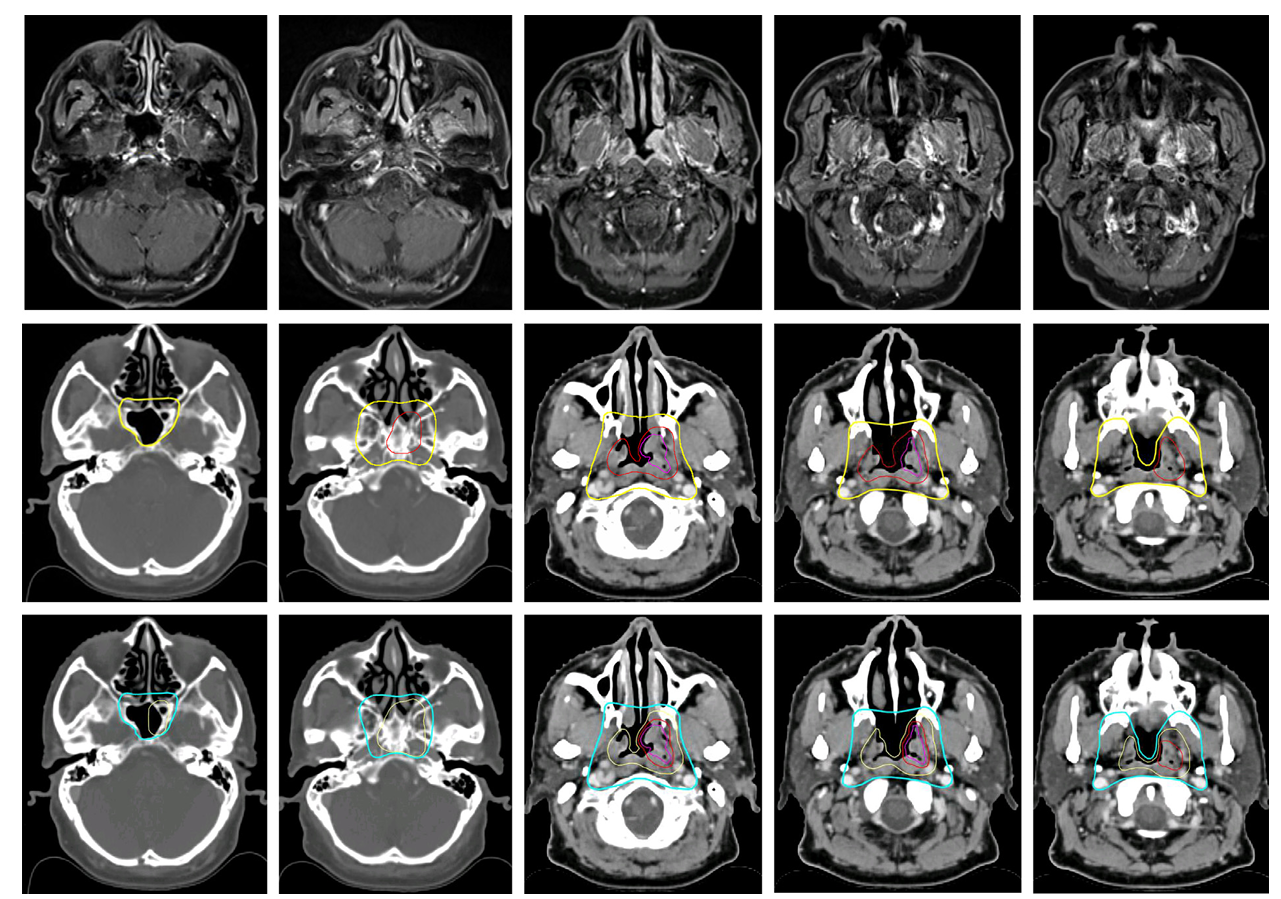

在原发性肿瘤临床靶区的勾画方面,针对接受70 Gy高剂量照射的靶区其几何外扩范围出现了意见分歧,约半数专家支持零毫米外扩而另一半则坚持三至五毫米外扩,因此新指南建议了一个零至五毫米的灵活范围以适应不同机构的技术条件,对于接受60 Gy中等剂量照射的靶区其外扩范围则从之前的十毫米调整为八至十毫米,并且强烈建议将整个鼻咽部纳入该中等剂量靶区而非之前的高剂量靶区。在低风险选择性照射方面新指南展现了明显的降级和精细化趋势,将许多解剖结构的预防性照射剂量从过去的50-60 Gy统一明确为50 Gy,并且对于偏侧生长的肿瘤开始考虑仅照射同侧结构以保护对侧正常组织,例如对于卵圆孔和岩尖的覆盖新指南建议对于偏心肿瘤可仅行同侧照射,此外对于斜坡的覆盖强调仅在其前三分之一未受侵时覆盖前三分之一若受侵则需全覆盖。

图1 T1偏侧肿瘤原发临床靶区勾画示意图